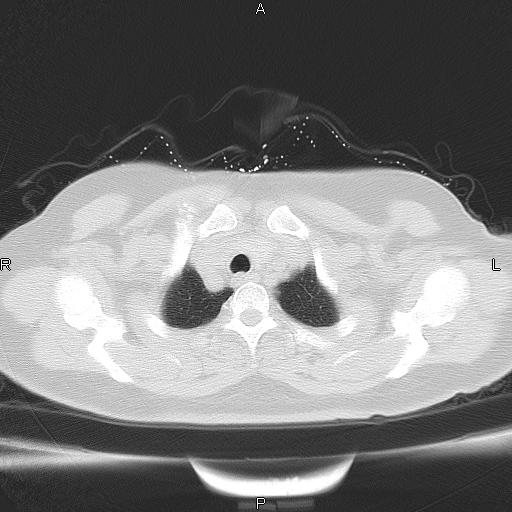

胸腺瘤

女、63Y 双眼睑下垂,早轻晚重。 胸腺瘤???

结果胸腺瘤